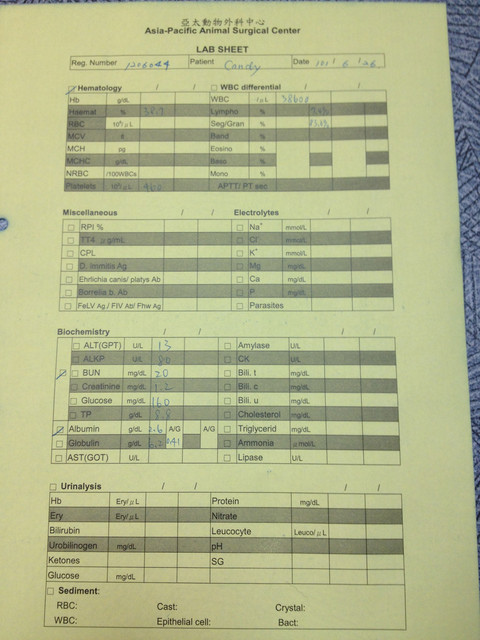

此後,我就沒有再回到這裡來了,這也是幾個月前的事情了。周醫師為Candy做了血液檢查,也看了一下這個腫瘤的部位,

她的看法與前面兩位醫師是大致相同的,她也是認為就算在初期發現了這顆腫瘤,我們能做的也是不多。

她的看法與前面兩位醫師是大致相同的,她也是認為就算在初期發現了這顆腫瘤,我們能做的也是不多。目前可以幫得上忙的是,做病理切片,化驗出這是哪一種腫瘤?

再來選擇適合的化療藥物,但是每一個寶貝們對與化療的反應不一,有些反應很好,有些反應不好,這是化療的風險。

另一種就是持續的吃消炎藥、抗生素與止痛劑,減緩Candy的疼痛。血液檢查出來,肝、腎指數的數字都很漂亮,

唯獨血液中的白血球過高,白血球檢驗是指在血液中白血球總數。

一般來說,檢驗出來的若是高於標準為癌症反應,低於標準則可能為病毒性疾病,但是Candy的指數高達38600,

周醫師說這應該是這顆腫瘤所帶出來的數值反映。

她認為要趕緊服用消炎藥,如果效果不彰,可能就要改為吃類固醇了,

要不然這顆腫瘤一爆開,不是一般傷口擦擦藥就會好,是會造成連鎖性的爆裂反應,

屆時Candy可能會因疼痛而不願意進食了。